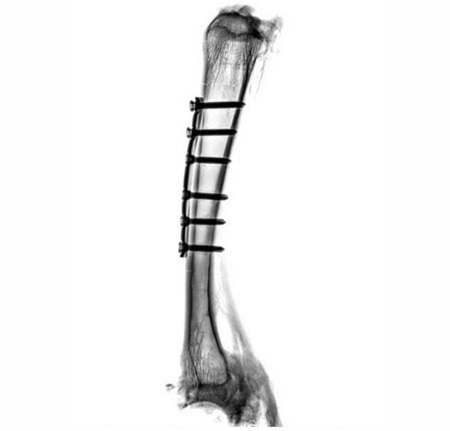

Implants on a sheep bone. The fit of the implants, the progress of healing and fissures on the screw connections are clearly visible. Image Credit: Scintica Instrumentation Inc